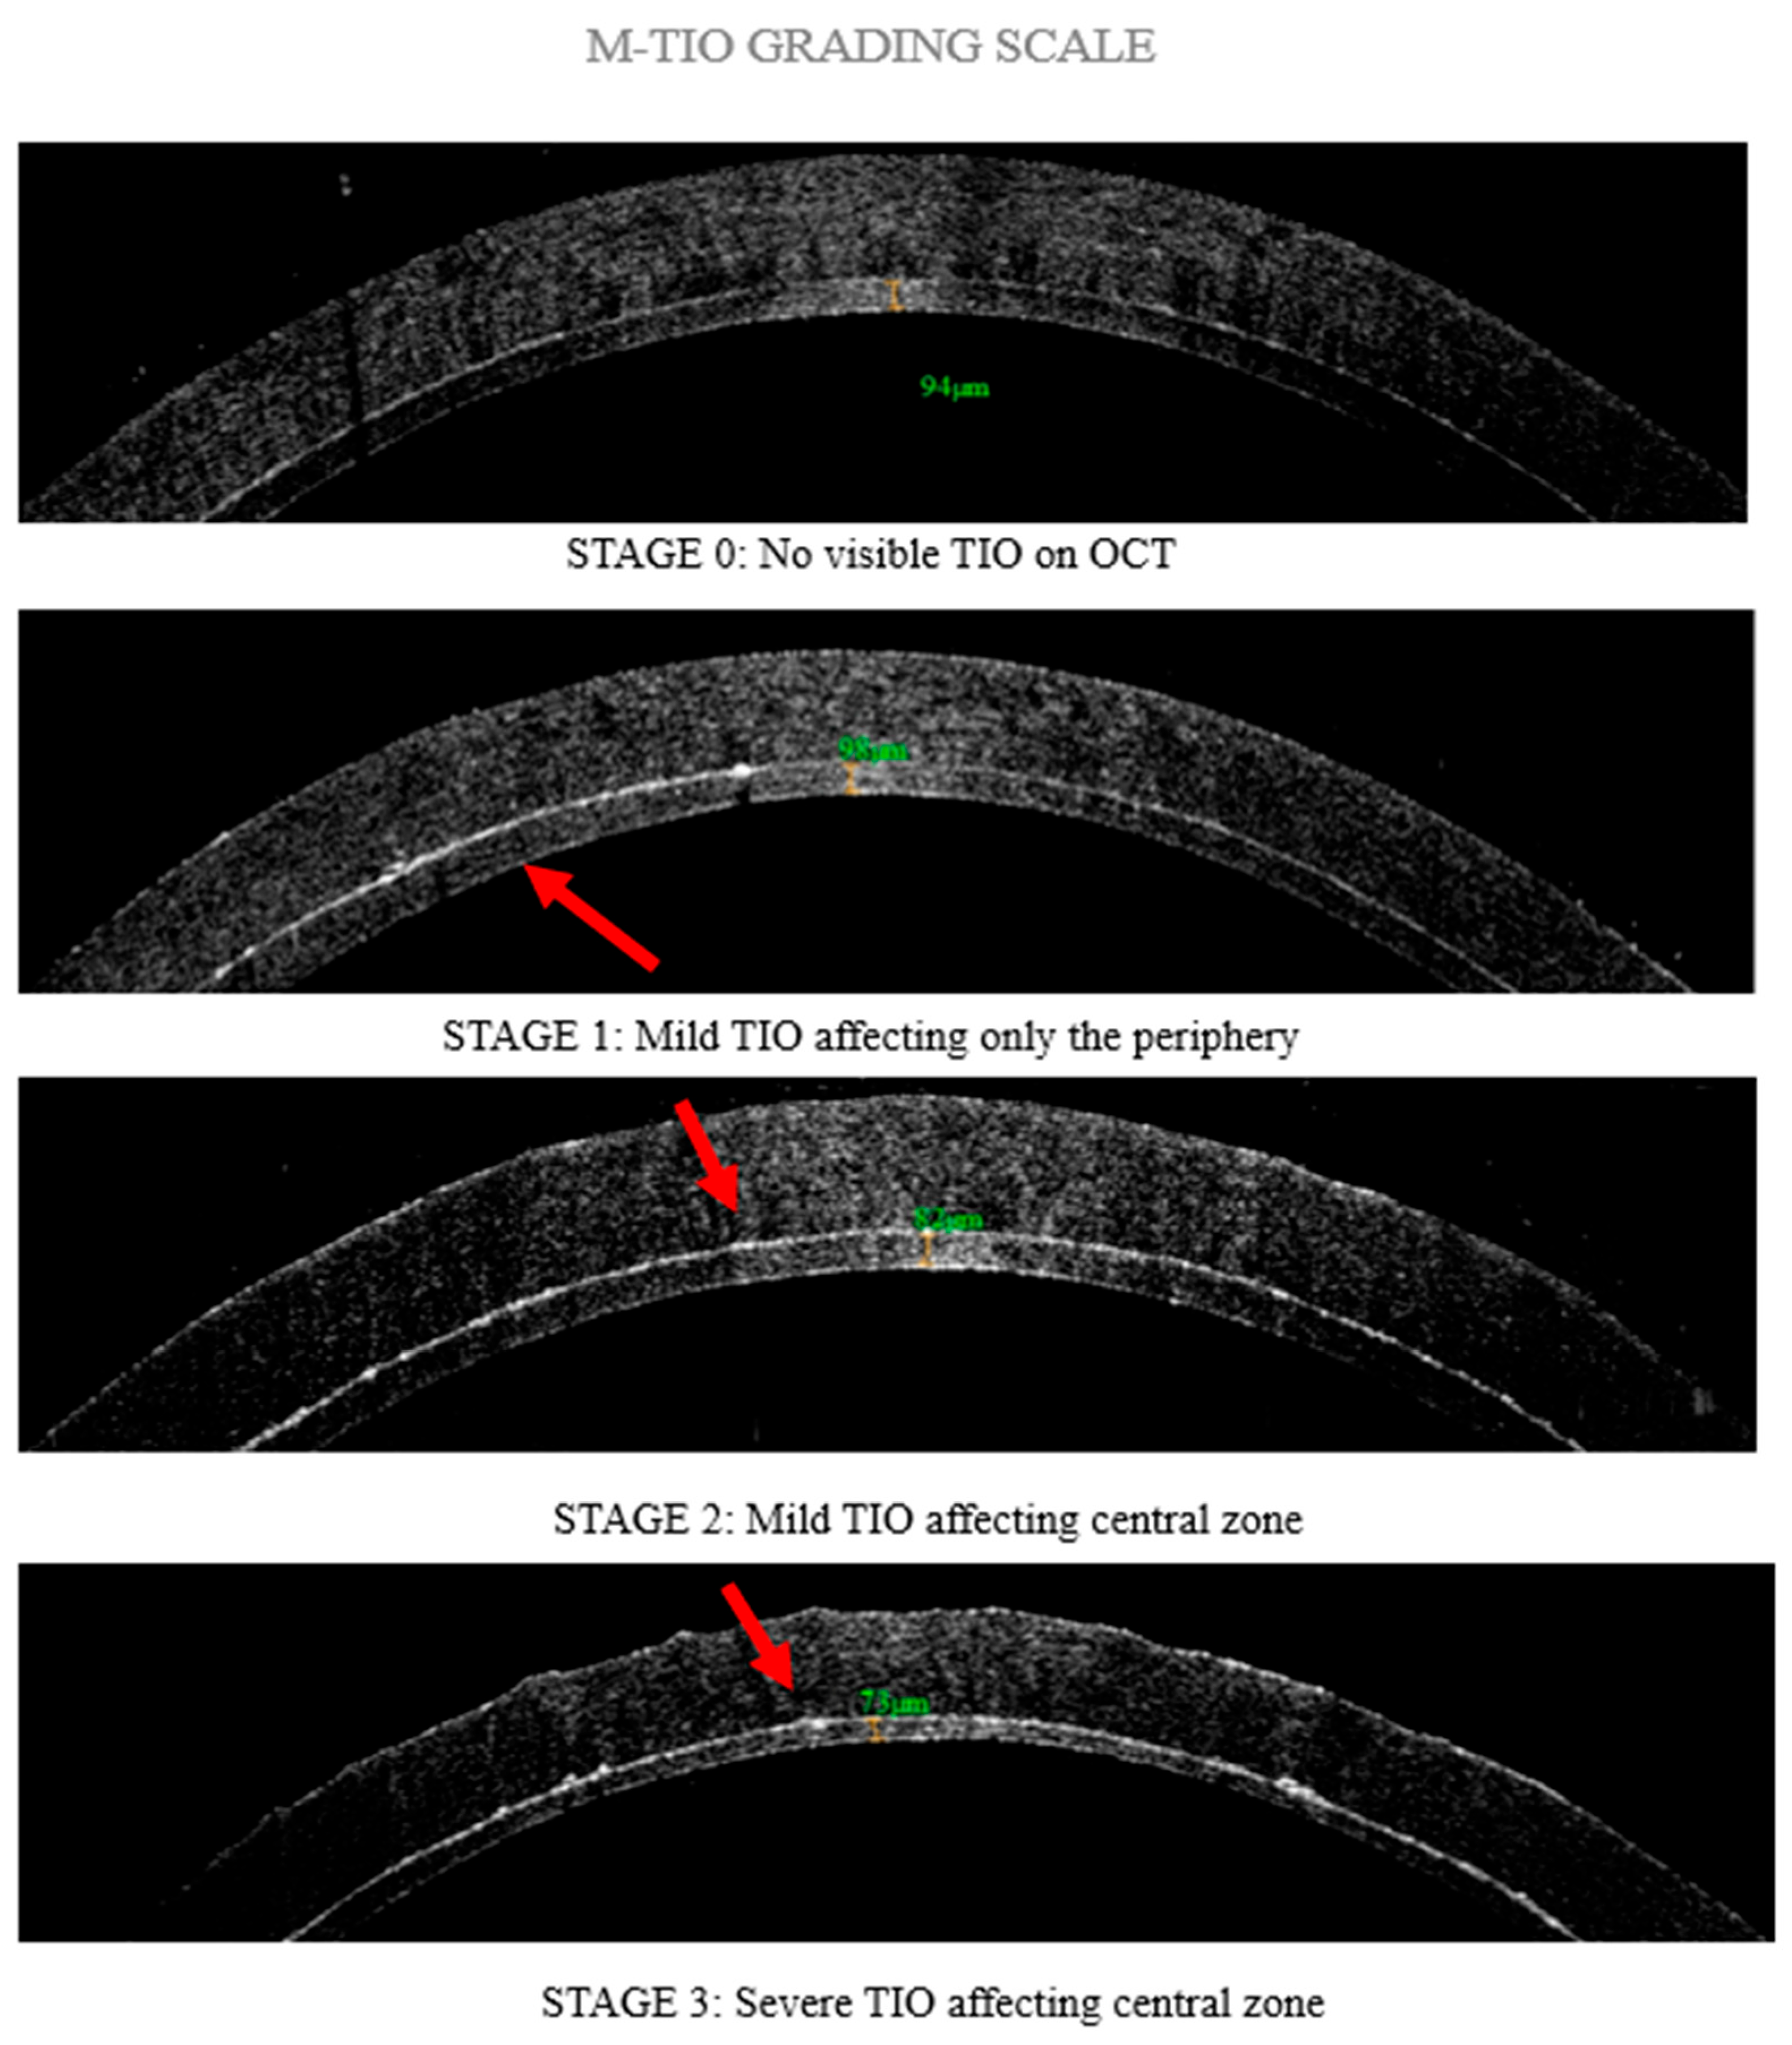

Screening and Grading of Textural Interface Opacities in DSAEK Grafts with the M-TIO Scale for Predicting Visual Outcomes